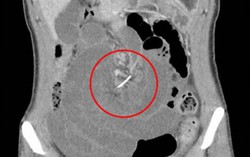

Thủng ruột vì nuốt dây niềng răng suốt 10 năm

Phòng & chữa bệnh 15:35 09/08/2017Hình ảnh chụp X-quang đã phát hiện ra một người phụ nữ 30 tuổi bị đau bụng mãn tính suốt nhiều năm do vô tình nuốt phải dây niềng răng từ 10 năm trước mà không hề hay biết.